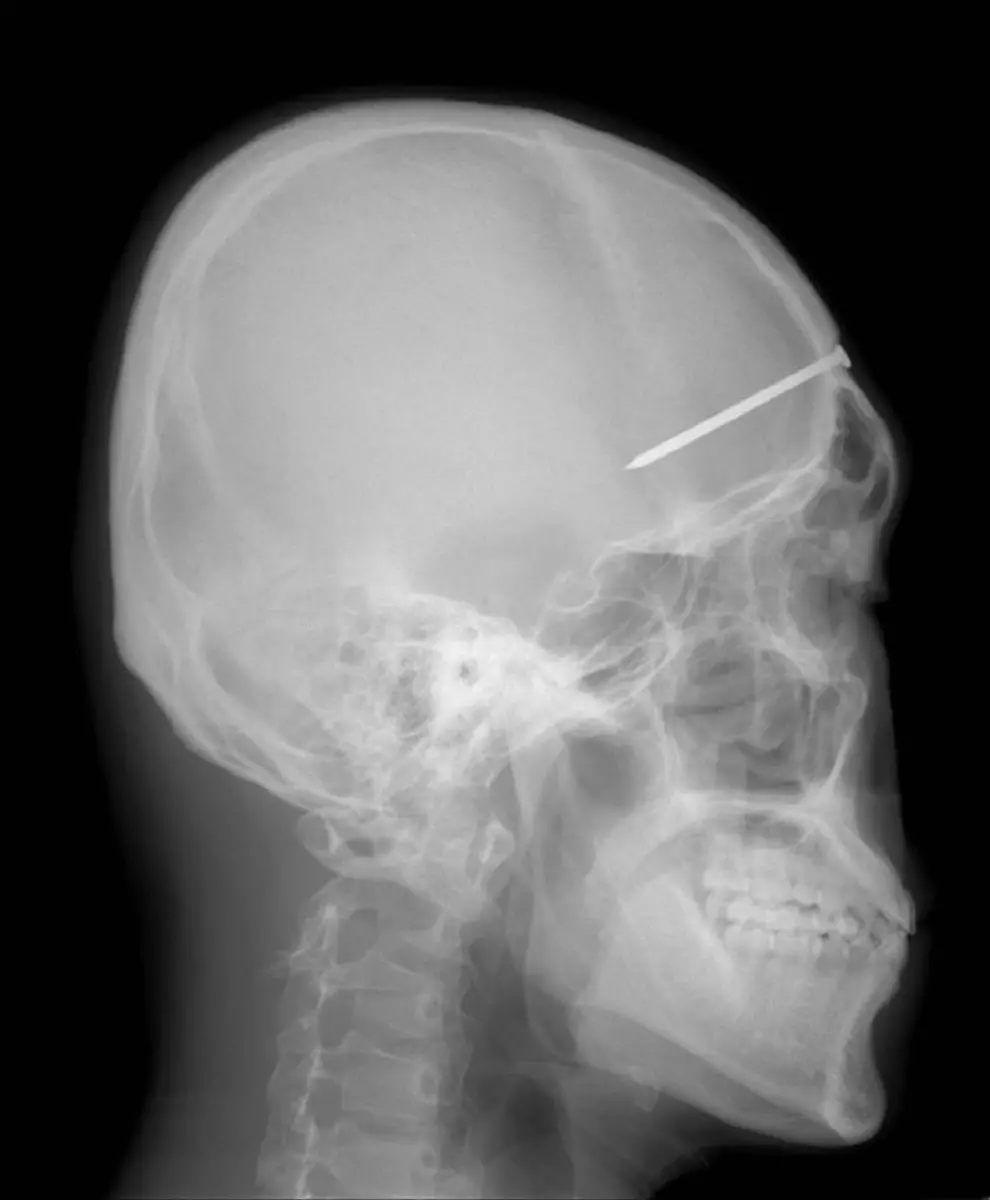

Nägel, Messer, TelefoneWas Röntgenstrahlen zum Vorschein bringen

Nicht immer zeigen Röntgenaufnahmen das, was man von ihnen erwartet. Oft kommt es zu Bildern, die selbst hartgesottene Betrachter zum Schaudern bringen - und der Wissenschaft Rätsel aufgeben.